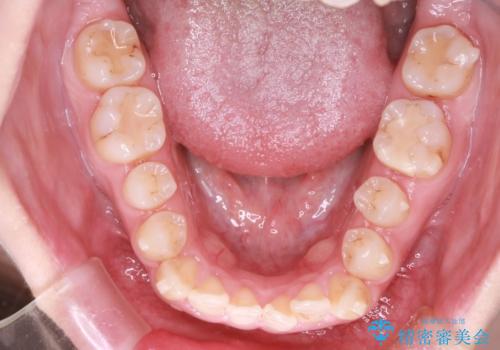

【オープンバイト】前歯のがたがたをなおしたい。

- 笑った時の前歯の見た目が気になることを主訴に来院されました。

上の歯が下の前歯を少し隠すぐらいを目指し、インビザラインにて治療を行いました。